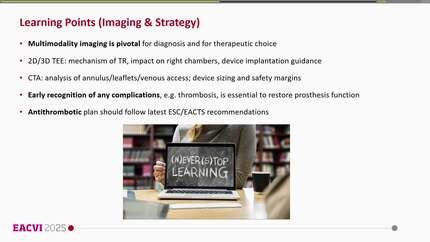

Rescue TTVR with a new-sized EVOQUE valve following transcatheter edge-to-edge repair